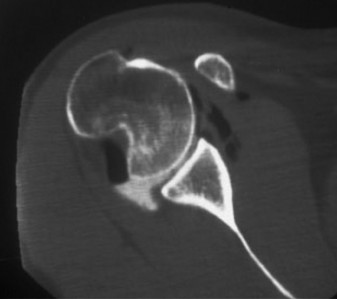

A sophomore, high school wide receiver presents to your clinic at the beginning of his football season. He reports a dislocation event after being tackled; his shoulder was “put back in place” by the on-field athletic trainer. A CT scan taken in the hospital today is shown (Fig. 2–33). He has been recruited by numerous colleges, plans to play at a division 1 school, and is very eager to return to the field.

Figure 2–33

What is the best treatment option for this patient?

Discussion

The correct answer is (E). A large bony fragment (>20%) makes the failure rate with nonoperative treatment (Answers A, B) unacceptably high. This question is meant to illustrate the challenges associated with treating an in-season athlete and highlighting the indications for surgery after a first time dislocation event. Typically, early in a season, providers will initiate an aggressive PT program and try and return athletes to the field within a few weeks so that they can play out the remainder of the season. Towards the end of the season, when there is insufficient time to rehab a patient, one may choose early surgery so that the patient has maximal time to recover prior to the next season. In this case, even though the

patient is extremely motivated to return to the field and has only sustained a single dislocation event, the large bony Bankart lesion behooves surgical treatment. The best option for him would be to have early surgery and have a maximal amount of time to prepare for his senior season. A Latarjet procedure (Answer C) is used for patients with recurrent anterior instability and significant glenoid bone loss, and the Magnuson–Stack procedure (Answer D) is a largely historic procedure that was used for recurrent anterior instability. Objectives: Did you learn...? The common presentation of a patient with shoulder instability?